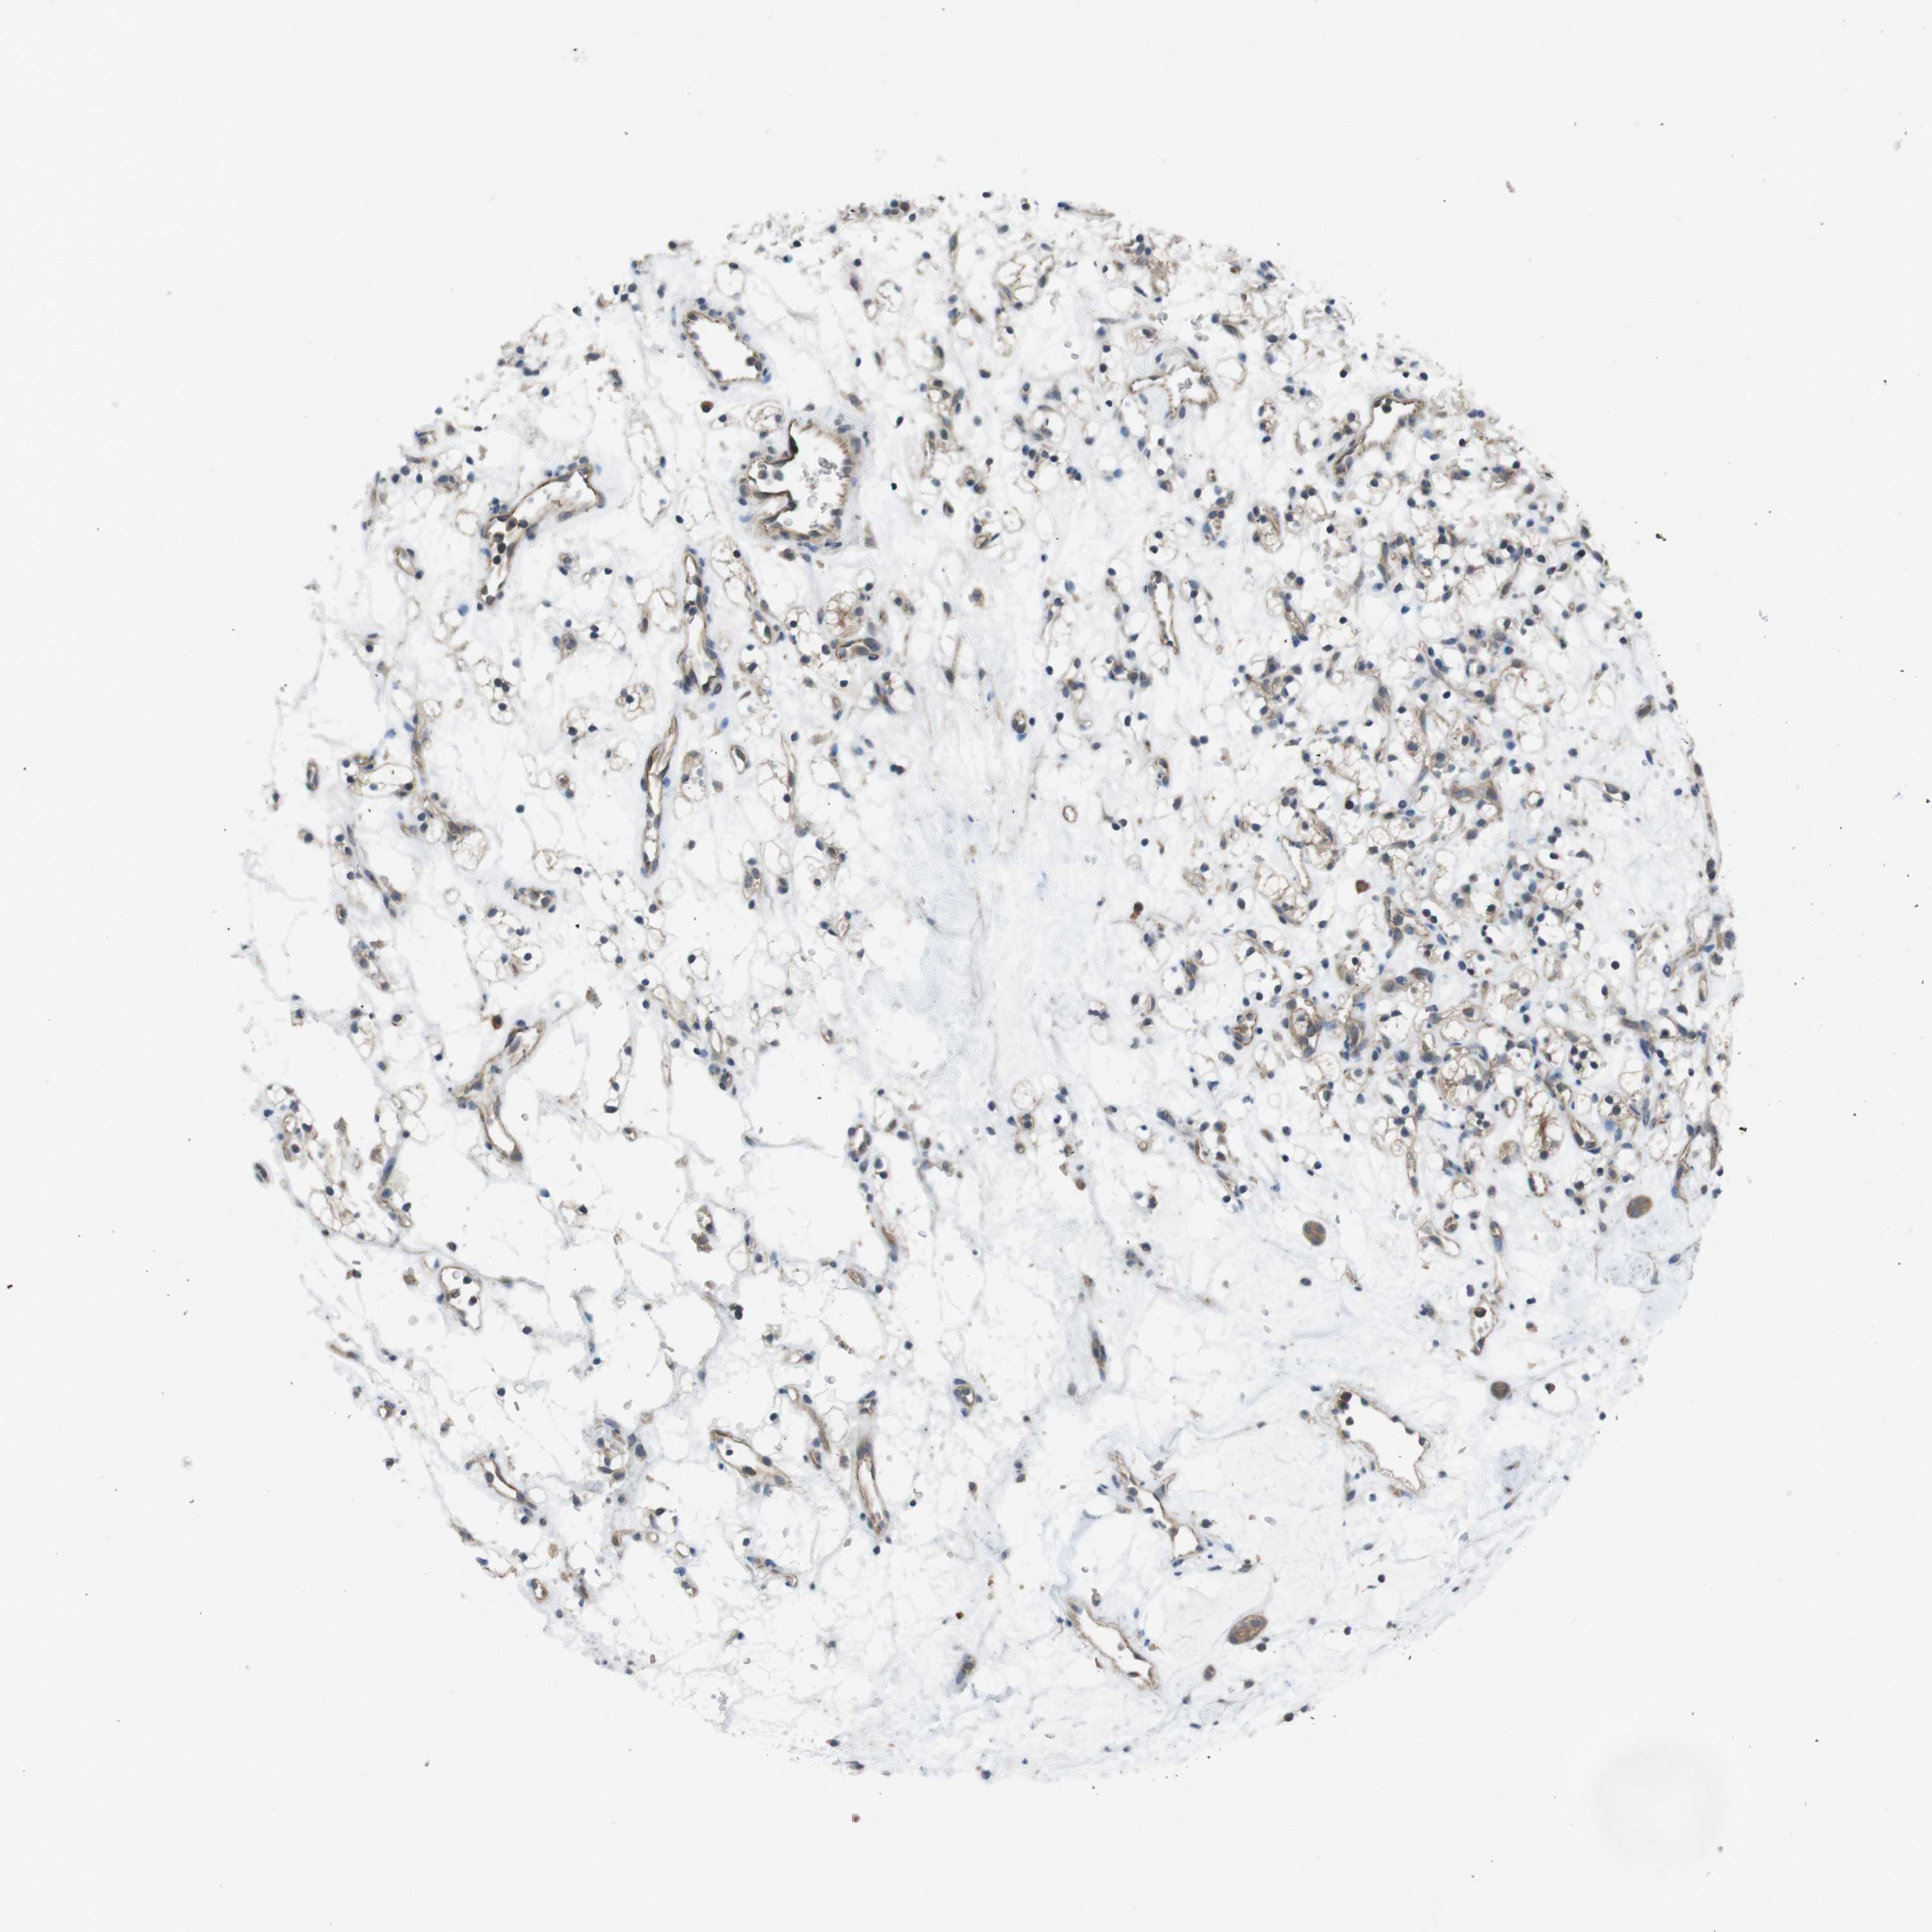

KIDNEY RENAL PAPILLARY CELL CARCINOMA (TCGA) - Interactive survival scatter ploti

The Survival Scatter plot shows the clinical status (i.e. dead or alive) for all individuals in the patient cohort, based on the same data that underlies the corresponding Kaplan-Meier plots. Patients that are alive at last time for follow-up are shown in blue and patients who have died during the study are shown in red.

The x-axis shows the expression levels (FPKM) of the investigated gene in the tumor tissue at the time of diagnosis. The y-axis shows the follow-up time after diagnosis (years). Both axes are complimented with kernel density curves demonstrating the data density over the axes. The top density plot shows the expression levels (FPKM) distribution among dead (red) and alive patients (blue). The right density plot shows the data density of the survived years of dead patients with high and low expression levels respectively, stratified using the cutoff indicated by the vertical dashed line through the Survival Scatter plot. This cutoff is automatically defined based on the FPKM cutoff that minimizes the p-score. The cutoff can be changed by dragging the vertical line or by entering a cutoff value in the square labeled "Current cut-off".

Under the Survival Scatter plot the p-score landscape (black curve; left axis) is shown together with dead median separation (red curve; right axis). Dead median separation is the difference in median mRNA expression between patients who have died with high and low expression, respectively. It is calculated as follows: median FPKM expression of dead patients with high expression - median FPKM expression of dead patients with low expression. This is intended to aid the user in visually exploring custom cutoffs and the associated p-scores and dead median separation.

Individual patient data is displayed and can be filtered by clicking on one or more of the category buttons on the top of the page. Categories describing expression level and patient information include: high, low, alive, dead, female, male and tumor stages. The scale of the x-axis can be toggled between linear and log-scale by clicking on the "x log" button. Mouse-over function shows TCGA ID, patient information and mRNA expression (FPKM) for each patient.

& Survival analysisi

Kaplan-Meier plots summarize results from analysis of correlation between mRNA expression level and patient survival. Patients were divided based on level of expression into one of the two groups "low" (under cut off) or "high" (over cut off). X-axis shows time for survival (years) and y-axis shows the probability of survival, where 1.0 corresponds to 100 percent.

SUGT1 is not prognostic in Kidney Renal Papillary Cell Carcinoma (TCGA)